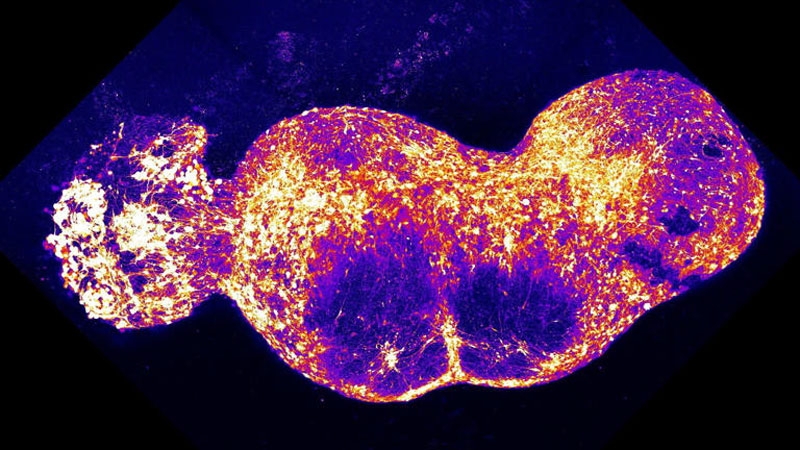

Все четыре органоида были помещены в чашку для культивирования, где срослись, образовав непрерывный контур передачи нервного импульса от начала до конца. На это ушло около 100 дней, в результате чего был сформирован ассемблоид длиной почти 1 см, содержащий около 4 млн клеток. Нейронные связи объединили составные органоиды, и в системе возникли паттерны синхронной передачи сигналов.

Сигнал боли был спровоцирован каплей капсаицина — вещества, придающего жгучесть перцу. После его введения начали регистрироваться волнообразные нейроимпульсные сигналы, распространявшиеся от места возбуждения до конечной точки, имитирующей головной мозг.

«Вы бы никогда не смогли увидеть эту волнообразную синхронность, если бы не могли наблюдать за всеми четырьмя органоидами одновременно, — сказал Пашка. — Мозг – это нечто большее, чем сумма его частей».